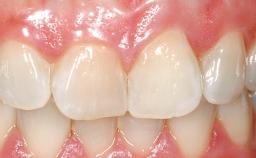

Immediate Placement of an Implant in a Maxillary Left Central Incisor Site

A 33-year-old female patient presented with an upper left central incisor that required extraction after a failed endodontic therapy. The tooth had been traumatized when the patient was a teenager and had undergone several endodontic treatments, including two apicectomy procedures. The patient was in good health and did not smoke. Clinical examination showed that the patient had a high lip line. In full smile, the gingival margins of the upper teeth were visible to the first molars. The gingival margins of central incisors 11 and 21 were only just showing. Examination of tooth 21 confirmed that the tooth was mobile and had hypererupted by 1 mm.

Lip Line No exposure of papillae Exposure of papillae Full exposure of mucosa margin

Soft Tissue Contour and Volume Slightly compromised